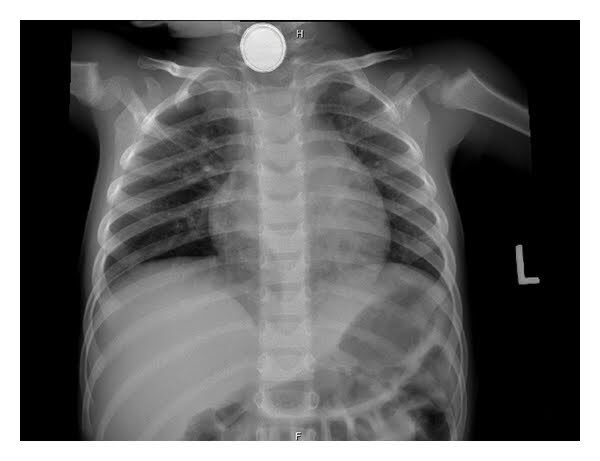

أما الخطوة الأهم فهي إجراءُ صور شعاعية

يعتمد العلاجُ أساساً على مكانِ توضُّعِ البطاريةِ، وإن كان المريضُ يعاني من أيِّ أعراضٍ أم لا. ويَشرَح المخطّطُ الآتي طريقةَ التصرف: